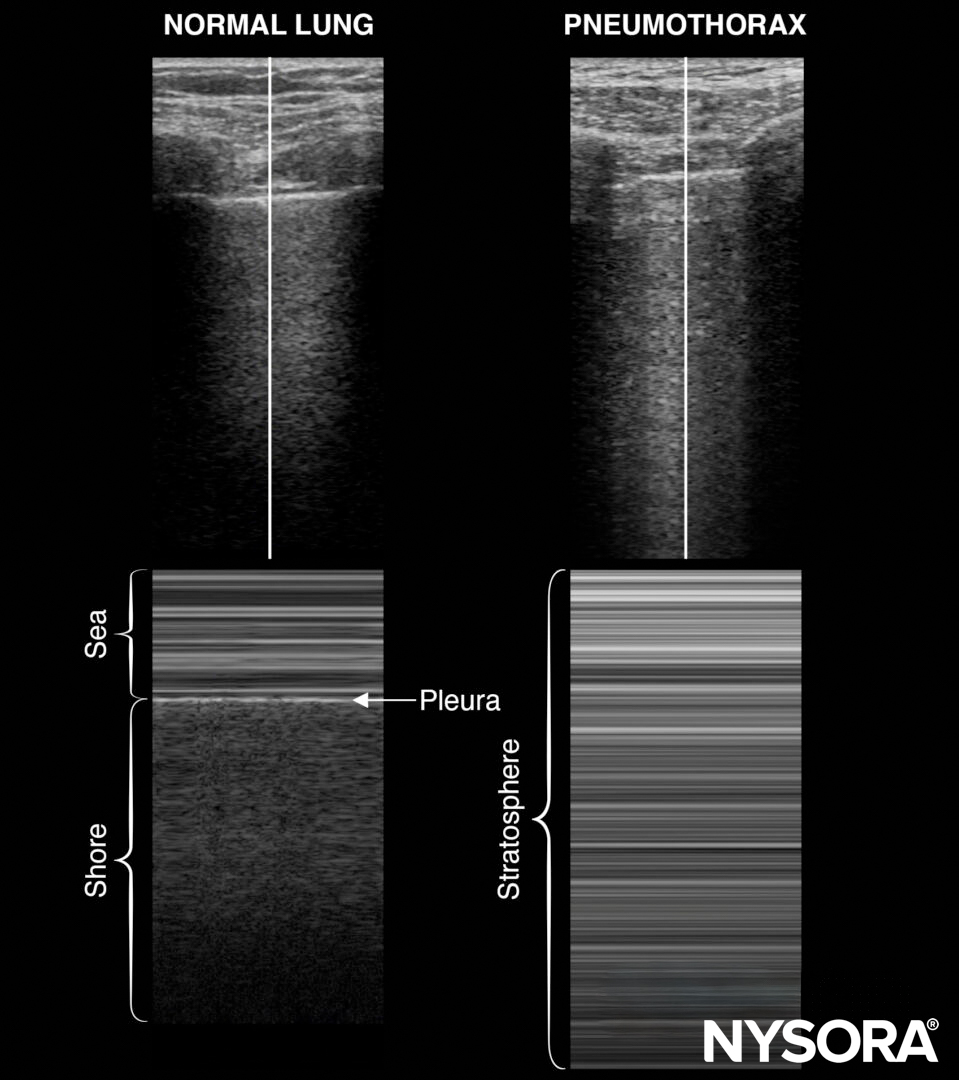

Lung sliding, together with the rapid atrial swirl sign, can rule out pneumothorax or confirm the position of the catheter after internal jugular or subclavian catheter insertion.

Lung sliding

Lung sliding = the two pleural layers sliding over each other, resulting in a shimmering or comet tails.

- The absence of lung sliding is highly sensitive for pneumothorax.

- Specificity is estimated to be above 80%. Other causes for absent lung sliding:

- The presence of lung sliding rules out a pneumothorax (100%).

M-mode of normal lungs exhibits a seashore sign. M-mode can be used instead of, or to supplement, the B-mode when lung sliding is difficult to demonstrate due to suboptimal images.

M-mode in normal lungs will show a seashore sign. Imagine the look of a sandy beach with the sea above. A pneumothorax will result in parallel horizontal white lines, also called the stratosphere sign.

- The stratosphere sign is sometimes referred to as the “barcode sign”. This latter may be confusing with the current trend towards complex barcodes (cf. QR codes).

- The lung point is the transition of the inflated lung into the pleural air of the pneumothorax. It is 100% accurate for pneumothorax and can be searched in the absence of lung sliding or the presence of a stratosphere sign.

Also, pay attention to the pleural line morphology when assessing lung sliding. A thick or irregular pleural line can be seen in pneumonia.